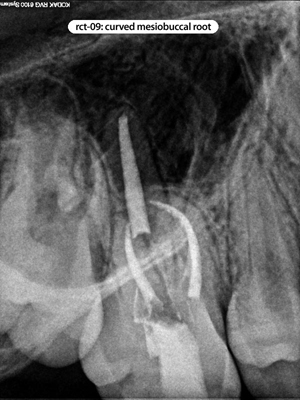

Root Canal Cases